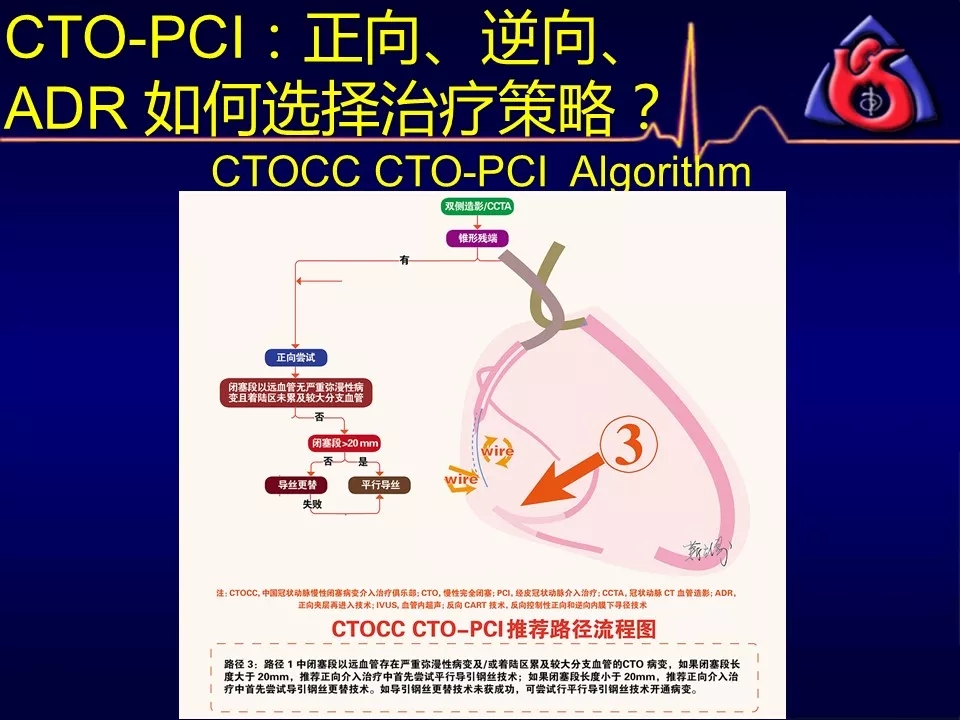

学习CTOCC CTO-PCI流程图的你

如何选择正向、逆向、IVUS指引及ADR技术?

《CTOCC CTO-PCI流程图精讲》